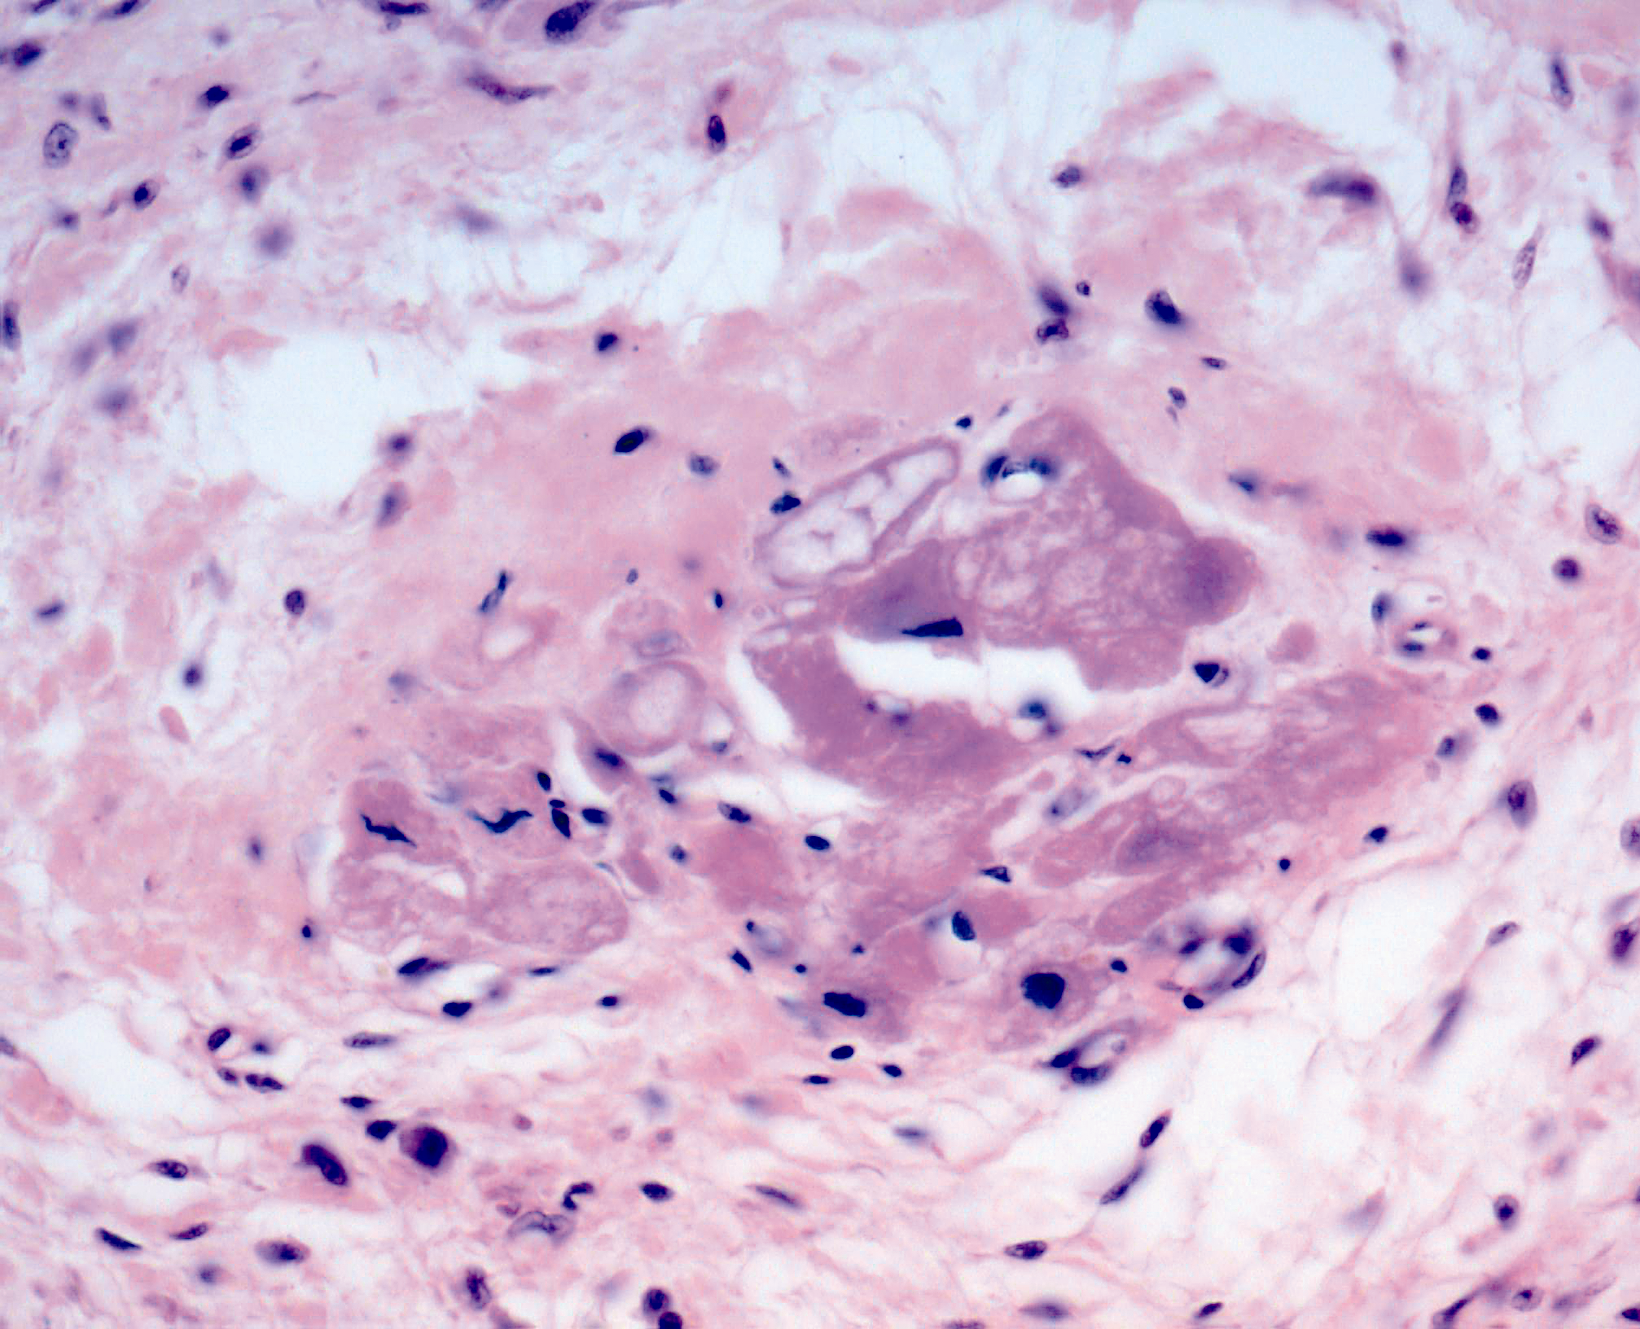

Микропрепараты: Лимфогранулематоз и Нодулярный Склероз